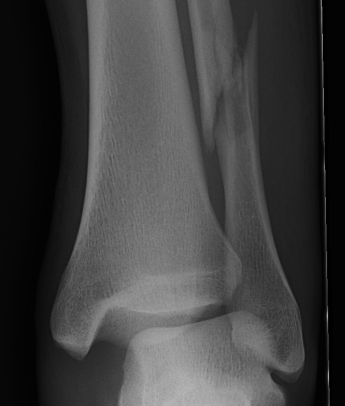

Tibia / fibular overlap < 1mm / syndesmotic injury

Ankle Fracture Syndesmosis WidenedAnkle Diastasis